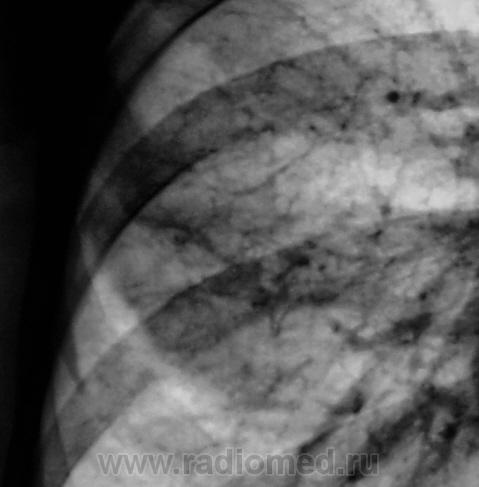

Первое исследование.